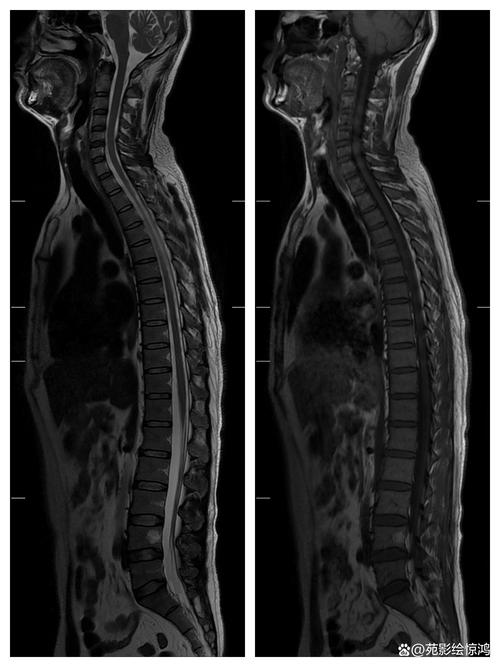

当您或您的医生提到“风湿性脊柱炎要做核磁共振”时,实际上指的是为强直性脊柱炎患者进行MRI检查。

- 骨桥形成/竹节样变:相邻椎体的骨赘连接起来,形成“竹节样”外观,这是疾病晚期的典型特征,在MRI上显示非常清楚。

- 脊柱:包括颈椎、胸椎、腰椎,主要用于评估脊柱的活动性炎症、椎体病变以及晚期的强直情况。

核磁共振是诊断和评估强直性脊柱炎(旧称风湿性脊柱炎)的“超级武器”,它能够弥补X光片的不足,在疾病的最早阶段就捕捉到炎症的踪迹,为医生提供“眼见为实”的证据,从而实现早期诊断、精准治疗和有效监测。